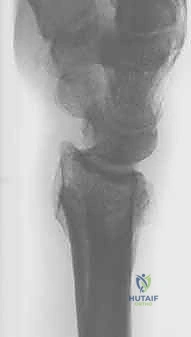

- الأشعة السينية الرقمية (X-rays): للرسغين السليم والمصاب، لمقارنة الزوايا وحساب مقدار التشوه بدقة.

- الأشعة المقطعية (CT Scan) مع إعادة البناء ثلاثي الأبعاد (3D Reconstruction): هذه الخطوة حاسمة. تتيح للدكتور هطيف رؤية العظم من جميع الزوايا، وتحديد مكان القص بدقة متناهية.